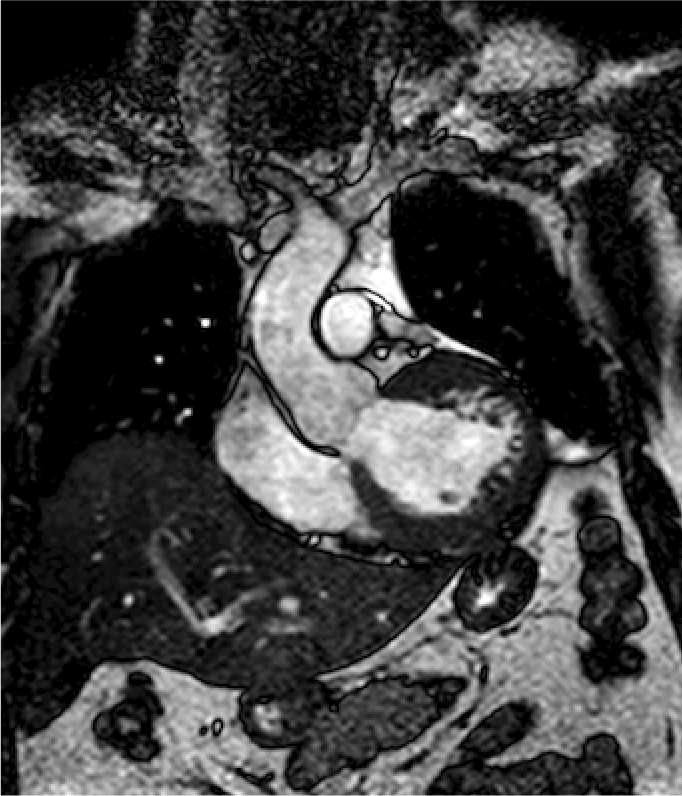

Resonancia magnética cardiaca

La resonancia magnética cardiaca es un una técnica de imagen que permite estudiar detalladamente y en una sola exploración la función y la estructura del corazón. Este auxiliar diagnóstico utiliza un potente campo magnético, sin radiación, para generar imágenes detalladas de las estructuras del corazón.

La resonancia magnética esta indicada en la evaluación de las cardiopatías congénitas tanto en el niño como en el adulto, en la evaluación de la perfusión miocárdica (resonancia cardiaca con gadolinio), de la función cardiaca, de las enfermedades del músculo cardiaco (miocardiopatías), tumores del corazón y del tejido que rodea al corazón (pericardio).

Este estudio es bien tolerado por la mayoría de las personas. El campo magnético no es dañino, pero puede causar el mal funcionamiento de algunos dispositivos médicos. La mayoría de los implantes ortopédicos no presentan riesgos, pero siempre debes informar al técnico de resonancia magnética si tiene algún dispositivo o metal en su cuerpo.